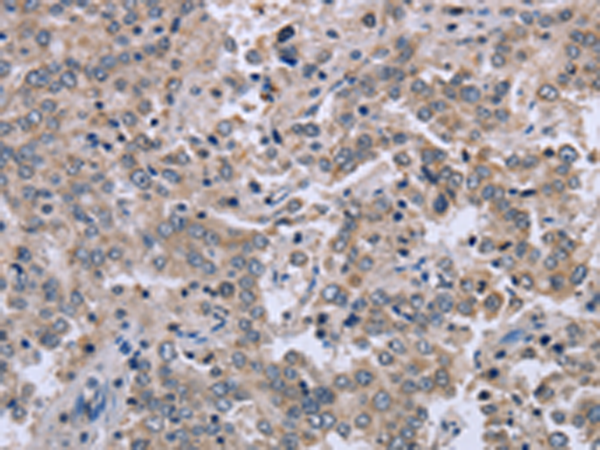

分类: 科研抗体货号: P08270别名: EIF3S3; eIF3-p40; eIF3-gamma应用: WB,IHC反应种属: Human, Mouse, Rat